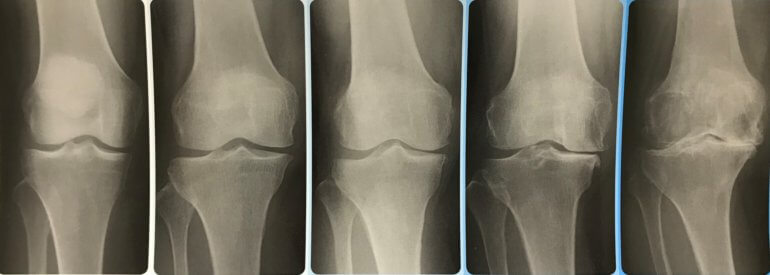

変形性膝関節症の分類では5段階で分類されています。

左から

Grade 0 :正常

GradeⅠ:関節裂隙狭小のないわずかの骨棘形成 , または軟骨下骨硬化

GradeⅡ:関節裂隙狭小(25% 以下)あるも骨変化なし

GradeⅢ:関節狭小(50%~75%)と骨棘形成 , 骨硬化像

GradeⅣ:骨変化が著しく,関節裂隙狭小(75% 以上)を伴う

と分類されています。